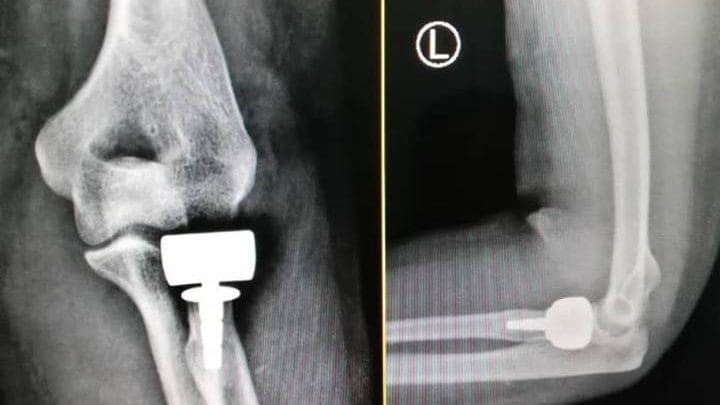

زراعة رأس صناعي لمريضة تعاني من كسر مركب في رأس عظمة الساعد

أجريت بمستشفى الخليل خلال الأيام الماضية عملية جراحية لمريضة تبلغ من العمر”35″، تعاني من كسر مركب في رأس عظمة الساعد .

العملية التي أجراها الدكتور” حسين الرجباني”،استشاري جراحة العظام والمفاصل كللت بالنجاح التام بتغير رأس عظمة الساعد برأس صناعي، وأكد الدكتور” الرجباني”، عقب العملية التي استمرت ساعة واحدة بأن هذه العملية من العمليات المعقدة، ولأول مرة تجري في ليبيا.